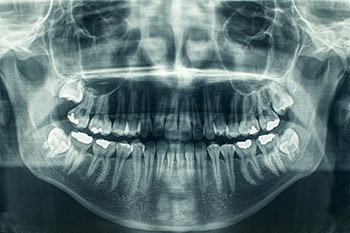

Dental X-rays and imaging are essential in modern dentistry, providing detailed views of teeth, gums, jawbone, and surrounding tissues that aid in accurate diagnoses and customized treatment plans. These diagnostic tools include several types of X-rays. Bitewing X-rays reveal tooth crowns, bone levels, and cavities between teeth. Periapical X-rays focus on individual teeth to detect decay, infections, and root issues. Panoramic X-rays offer a comprehensive view of the entire mouth, useful for assessing TMJ disorders, impacted teeth, and detecting tumors.